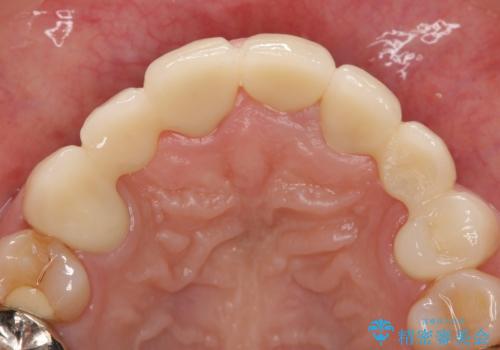

- 昔治療した前歯の被せ物の見た目を改善したいといらっしゃった方の症例です。

左上4番目の歯から右上3番目の歯まで計7歯のクラウンを除去し、オールセラミッククラウンによる補綴を行いました。

今回用いたオールセラミッククラウンはジルコニアフレームという白い素材の上にセラミックを盛っているため、審美性が非常に高いのが特徴です。

また、ジルコニアは人工ダイヤモンドの材料にも使われているほど高い強度を持っており、そのためオールセラミッククラウンは審美性だけでなく、奥歯やブリッジの補綴も可能とするクラウンです。